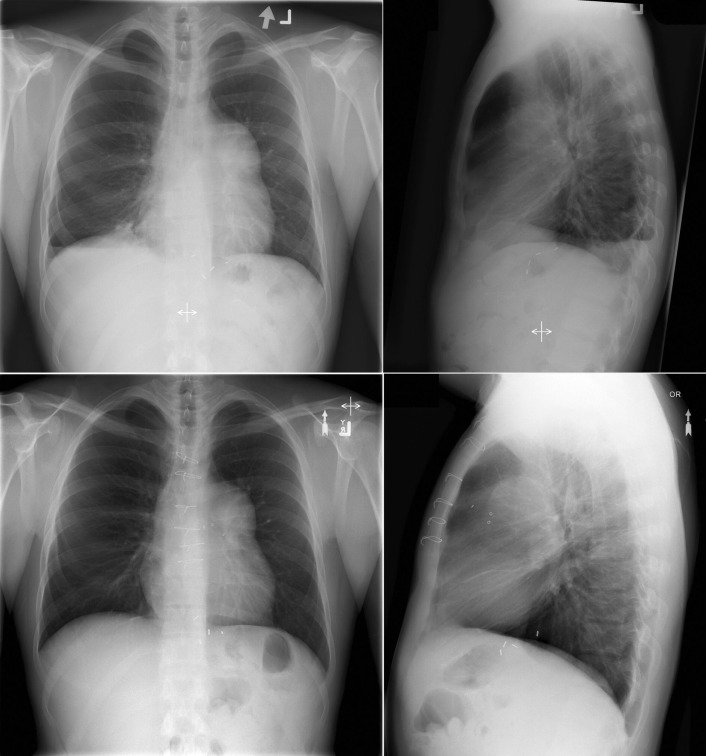

Pulmonic stenosis and a secundum atrial septal defect. There is dilation (poststenotic) of the main pulmonary artery. Right atrial enlargement is suggested by the right heart contour on the posteroanterior radiograph, and right ventricular enlargement is suggested by the sternal apposition on the lateral radiograph.

Upper (preoperatively) and lower (postoperatively) chest radiographs of a patient with severe valvular pulmonic stenosis who underwent insertion of a Hancock II bioprosthesis.